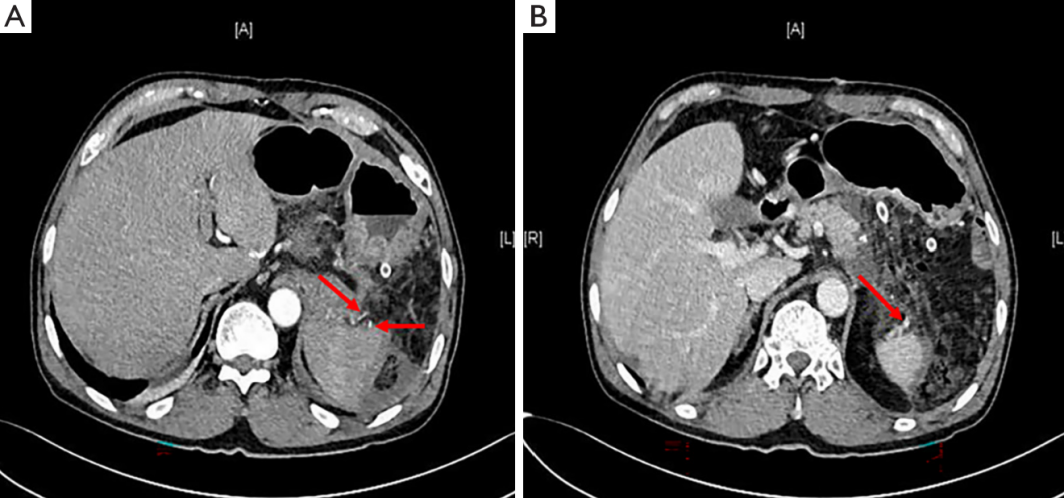

术前CT扫描和三维重建:

(A) 术前CT显示胰体尾部囊性病变(红色箭头),与脾血管毗邻关系密切;